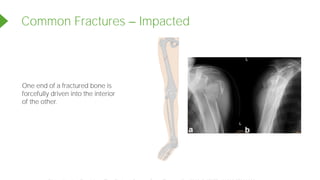

Common Fractures Impacted

One end of a fractured bone is

forcefully driven into the interior

of the other.